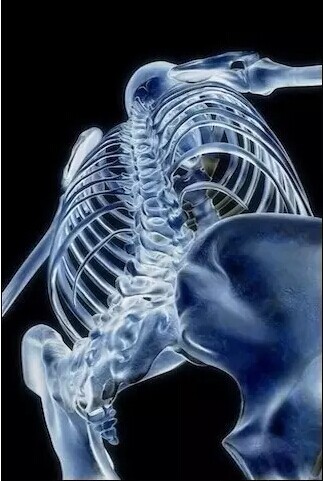

肋骨

人体骨骼